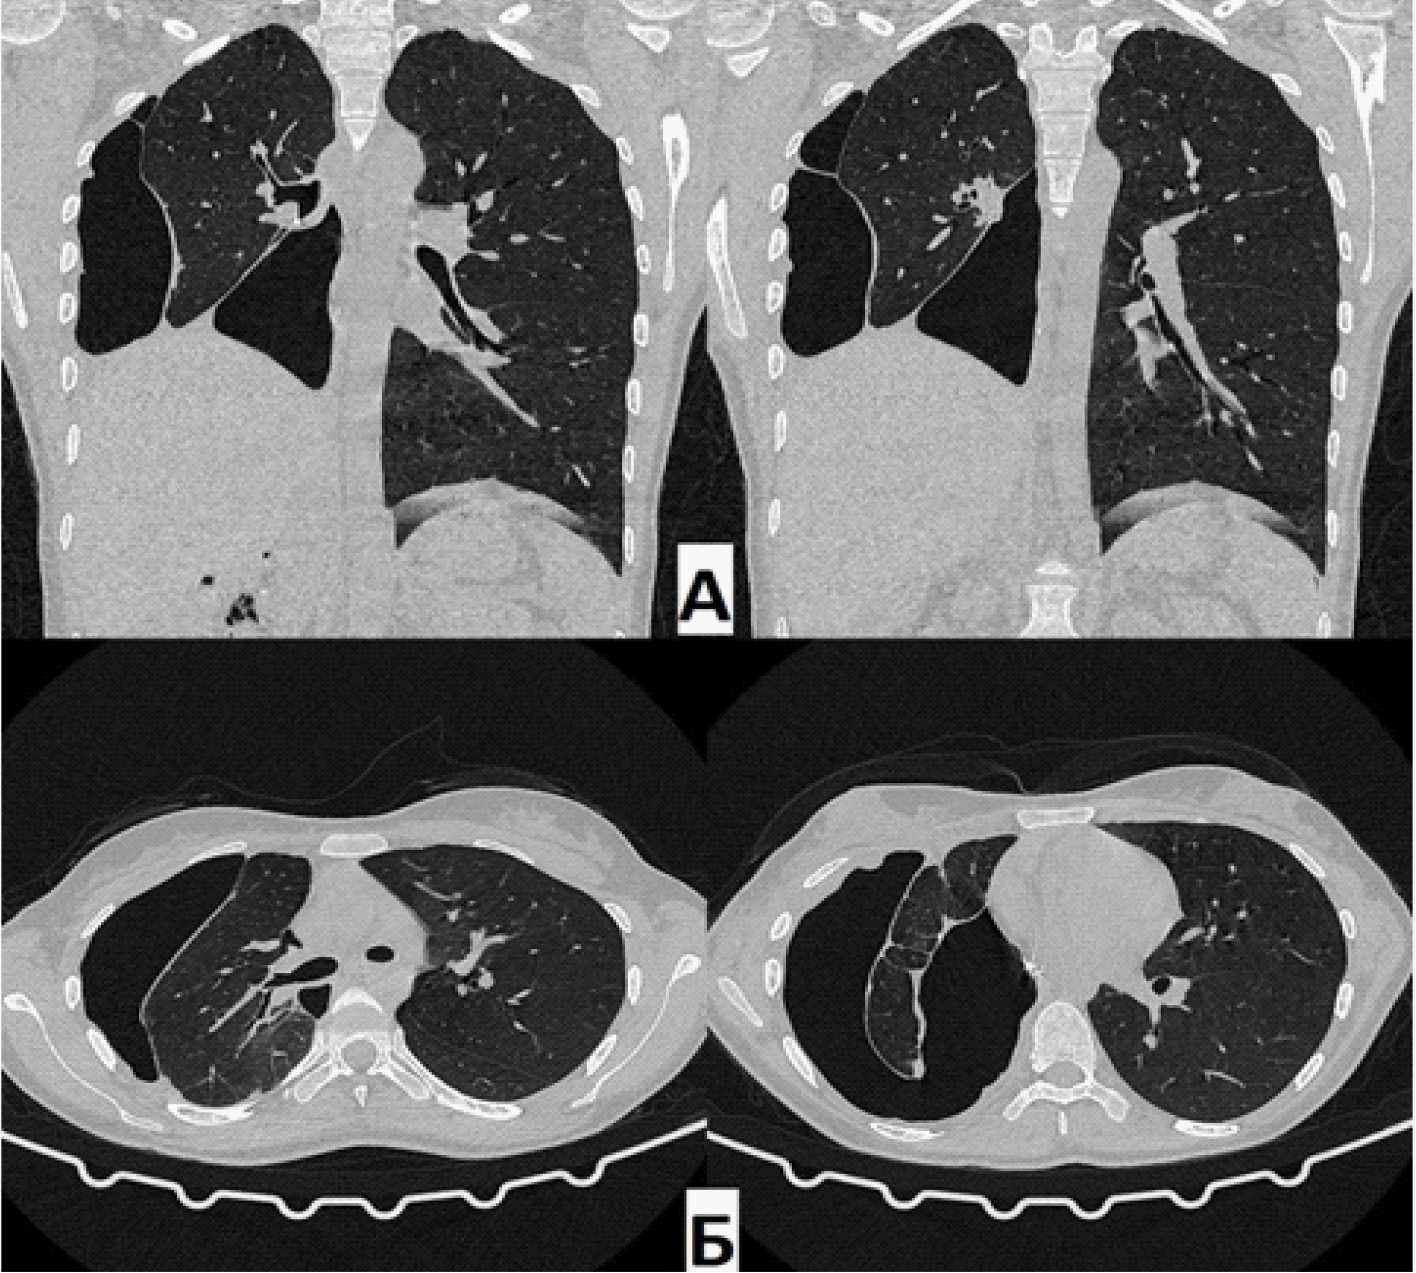

При контрольном КТ ОГК через 1,5 года: в динамике – полное отсутствие ОПП. Состояние после этапного хирургического лечения. В оставшихся отделах правого легкого без патологических изменений. Эмфизематозные изменения верхней доли правого легкого. Тень средостения располагается срединно, правый купол диафрагмы приподнят до уровня V межреберья.

Рис. 5. Компьютерная томография (А – фронтальная проекция; Б – аксиальная проекция) через 1,5 года. Отсутствие остаточной плевральной полости справа